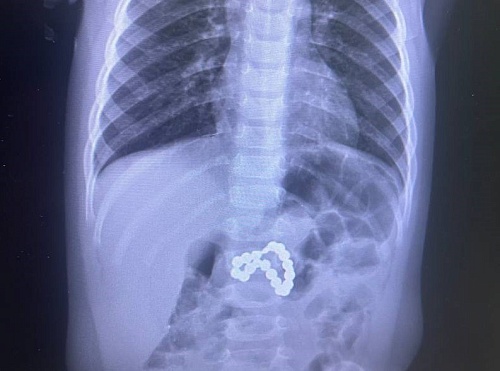

Виталий Еськин несколько месяцев испытывал боли в животе, но в начале января его состояние резко ухудшилось. 6 января его доставили в районную больницу, где выявили обширное желудочно-кишечное кровотечение. Учитывая критичность состояния, транспортировка пациента в более крупный медицинский центр была невозможна — это могло привести к фатальным последствиям.

На помощь пришли специалисты из Областной больницы № 1 Тюмени. Они оперативно прибыли в Аромашево и провели сложнейшую операцию на месте. Хирурги выполнили резекцию желудка, которая длилась 2,5 часа. Однако условия, в которых пришлось работать медикам, были далеки от стандартных.

«Пациент очень крупный, он фактически не помещался на операционный стол. Мы проводили операцию на кровати, что было достаточно сложно, но операция была выполнена», — рассказали врачи.